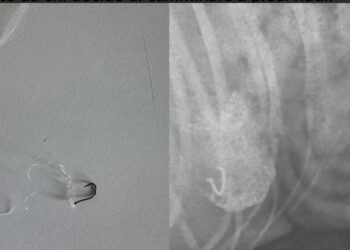

Ami in spiaggia si possono trasformare in pericoli per animali e persone: ultimi casi nelle coste del Sud Sardegna

"Non buttate ami in spiaggia": questo l'appello condiviso da chi ha salvato il proprio animale somministrandogli una alimentazione particolare al fine di espellere il corpo estraneo che era finito nello stomaco dell'animale.